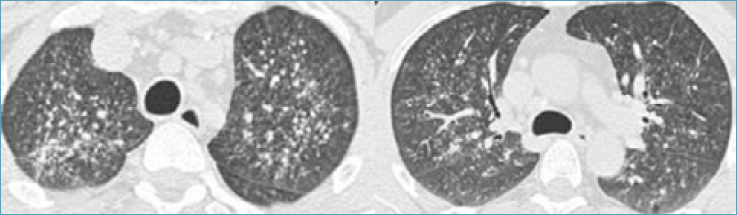

Paziente V.Y., 43 anni, di origine ucraina, non fumatore, non atopico, giungeva alla nostra osservazione, trasferito dal Pronto Soccorso, lamentando da alcuni mesi dispnea ingravescente e, da circa una settimana, febbricola persistente e sudorazione. Il paziente riferiva inoltre un recente episodio di emoftoe. Dall’anamnesi patologica remota si evinceva esclusivamente ipertensione arteriosa in trattamento farmacologico. Gli esami ematochimici risultavano nella norma in assenza di rialzo degli indici di flogosi (10,4x103 leucociti/uL, proteina C reattiva pari a 0,5 mg/dL). L’emogasanalisi arteriosa mostrava una lieve alcalosi respiratoria con tensione dell’ossigeno nella norma (pH 7,46, PaCO2 34 mmHg, PaO2 82 mmHg, HCO3- (c) 22 mmol/L). Alla fibrolaringoscopia lo specialista otorinolaringoiatra non evidenziava nulla di organico a carico della laringe e dell’ipofaringe con normale motilità cordale e assenza di tracce ematiche o fonti di sanguinamento evidenti. Il paziente veniva sottoposto pertanto ad una prima valutazione radiologica con TC torace ad alta risoluzione (HRCT) che mostrava multipli micronoduli distribuiti nell’interstizio peribroncovascolare e nei setti interlobulari, diffusi in entrambi i polmoni, prevalentemente a carico dei lobi superiori e del lobo medio (Fig. 1); alcune bronchiolectasie al lobo superiore di destra; rare bolle enfisematose e multiple tumefazioni linfonodali con pareti parzialmente calcifiche a sede ilo-mediastinica (diametro max 15 mm) (Fig. 2). Il radiologo poneva pertanto l’ipotesi diagnostica di sarcoidosi come quella apparentemente più plausibile.

Figura 1.HRCT (finestra parenchimale): multipli micronoduli distribuiti nell’interstizio peribroncovascolare e nei setti interlobulari, prevalentemente a carico dei lobi superiori e del lobo medio.